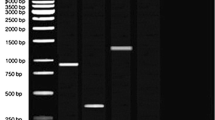

Minocycline, a broad range tetracycline was procured from Sigma-Aldrich, St. Louis, MO, USA. Endolysin MR-10 was purified from previously characterised phage MR-10 (Chhibber et al. 2013). Firstly, the endolysin was extracted from the phage following the method described by Adams and Park (1956) and further purified by using ion exchange chromatography (DEAE-Sepharose) and gel chromatography. Briefly, the crude enzyme was applied to column packed with Tris–HCl (0.2 M, pH 7.2) equilibrated DEAE-Sepharose. The bound enzyme was eluted using a gradient (0.1–1 M NaCl). The fractions showing lytic activity were pooled, concentrated and then applied onto Sephadex G-100 for further purification. Thereafter, the elution was done using Tris–HCl (0.2 M, pH 7.2). Enzyme purification was confirmed by SDS-PAGE analysis at each step.

The biofilm developed on coverslips were observed under electron microscope (SEM) for direct visualisation of mature biofilm formed. The ica-positive MRSA biofilm was observed on the third day (i.e., peak day) and ica-negative MRSA biofilm on the fifth day of incubation. Upon SEM analysis, both MRSA biofilms showed all the three indicators of a mature biofilm, including presence of extracellular matrix, 3days structure as well as possible water channels. As it is evident from Fig. 1a, both ica-negative MRSA as well as ica-positive MRSA biofilms were equally dense and showed all the indicators of a mature biofilm (Fig. 1b).

Scanning electron microscopy was done to elucidate the structure of the biofilm formed by both the strains. The mature biofilm formed by the MRSA strains were more or less similar in structure. They were equally dense and contained the apt morphology of the mature biofilm such as 3-D structure, possible water channels and dense matrix. Previous researchers have shown that lack of ica-locus results in the formation of weak biofilm by ica-negative MRSA strains (Leriche et al. 2000). But, the results of this study confirm that the biofilm formed by both the strains were similar in morphology as well as in resistance to antibiotics. However, ica-negative MRSA achieved its peak on the fifth day whereas ica-positive MRSA achieved its peak on the third day (Chopra et al. 2014).